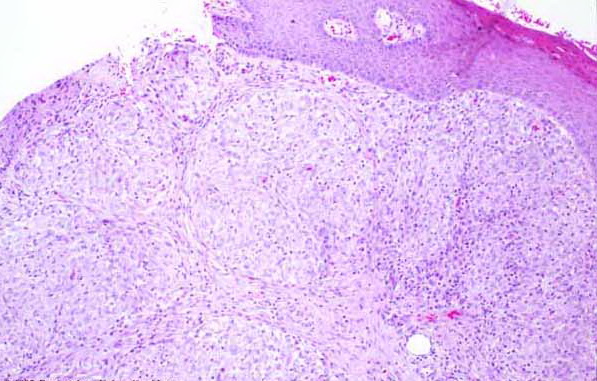

Like lesions in other organs, the cutaneous lesions of chronic, persistent sarcoidosis are characterized by the presence of circumscribed collections of epithelioid histiocytes-so-called epithelioid cell tubercles-which show little or no necrosis .

The papules, plaques, and lupus pernio-type lesions show variously sized aggregates of epithelioid cells scattered irregularly through the dermis with occasional extension into the subcutis (. In the erythrodermic form, the infiltrate shows small granulomas in the upper dermis intermingled with numerous lymphocytes

In typical cutaneous lesions of sarcoidosis, the well-demarcated islands of epithelioid cells contain few, if any, giant cells. Those that are present are usually of the Langhans type. A moderate number of giant cells can be found in old lesions. These giant cells may be large and irregular in shape. In a minority of cases, giant cells contain asteroid bodies or Schaumann bodies . Asteroid bodies , which are more common, are star-shaped eosinophilic structures that, when stained with phosphotungstic acid-hematoxylin, produce a center that is brown-red with radiating blue spikes . Schaumann bodies are round or oval, laminated, and calcified, especially at their periphery. They stain dark blue because of the presence of calcium. Neither of these two bodies is specific for sarcoidosis: They have been observed in a variety of other granulomas, including those of leprosy, tuberculosis, foreign-body reactions, and necrobiotic xanthogranuloma .

Classically, sarcoid has been associated with only a sparse lymphocytic infiltrate, particularly at the margins of the epithelioid cell granulomas . Because of the scarcity of lymphocytes, the granulomas have been referred to as “naked” tubercles. However, lymphocytic infiltrates in sarcoid may occasionally be dense, as in tuberculosis . Occasionally, small foci of fibrin or necrosis showing